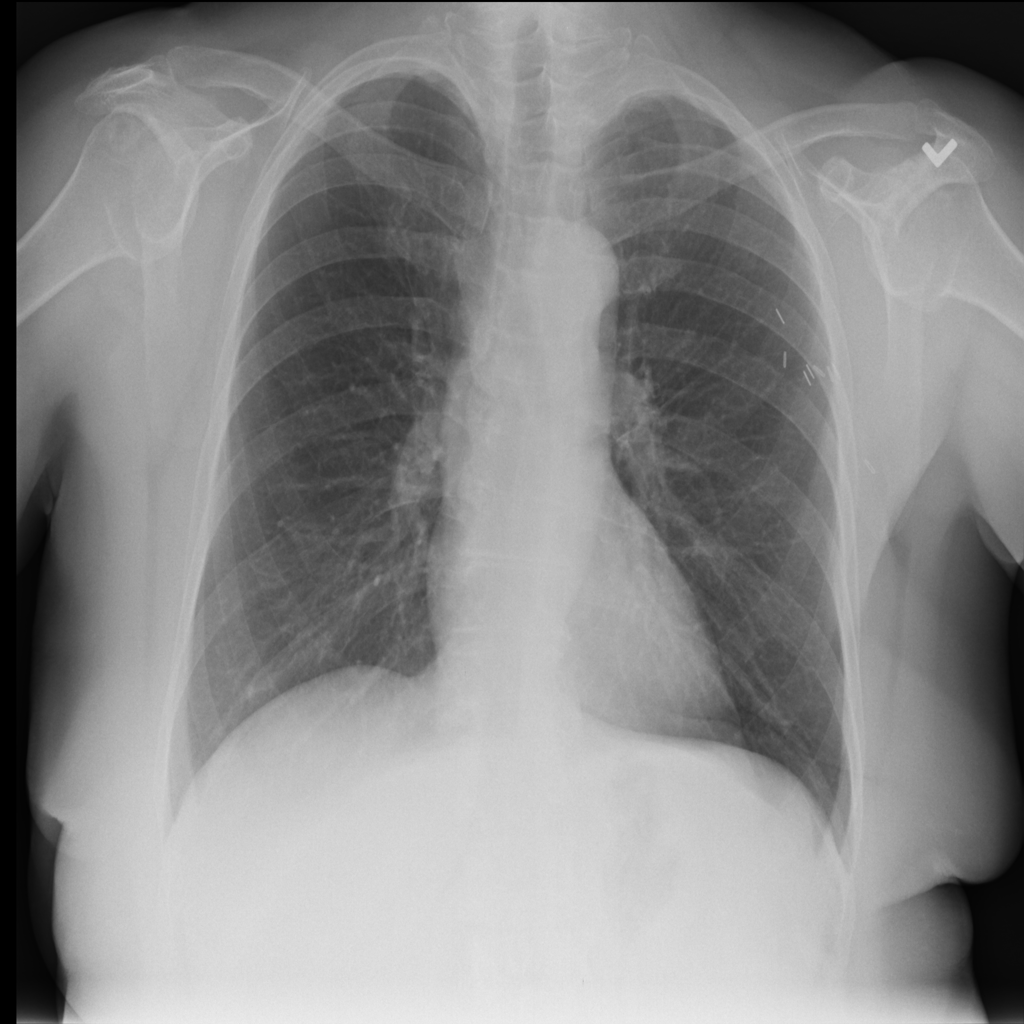

PAT-250B · IMG-000Nodule

PAT-250B · IMG-000

PA